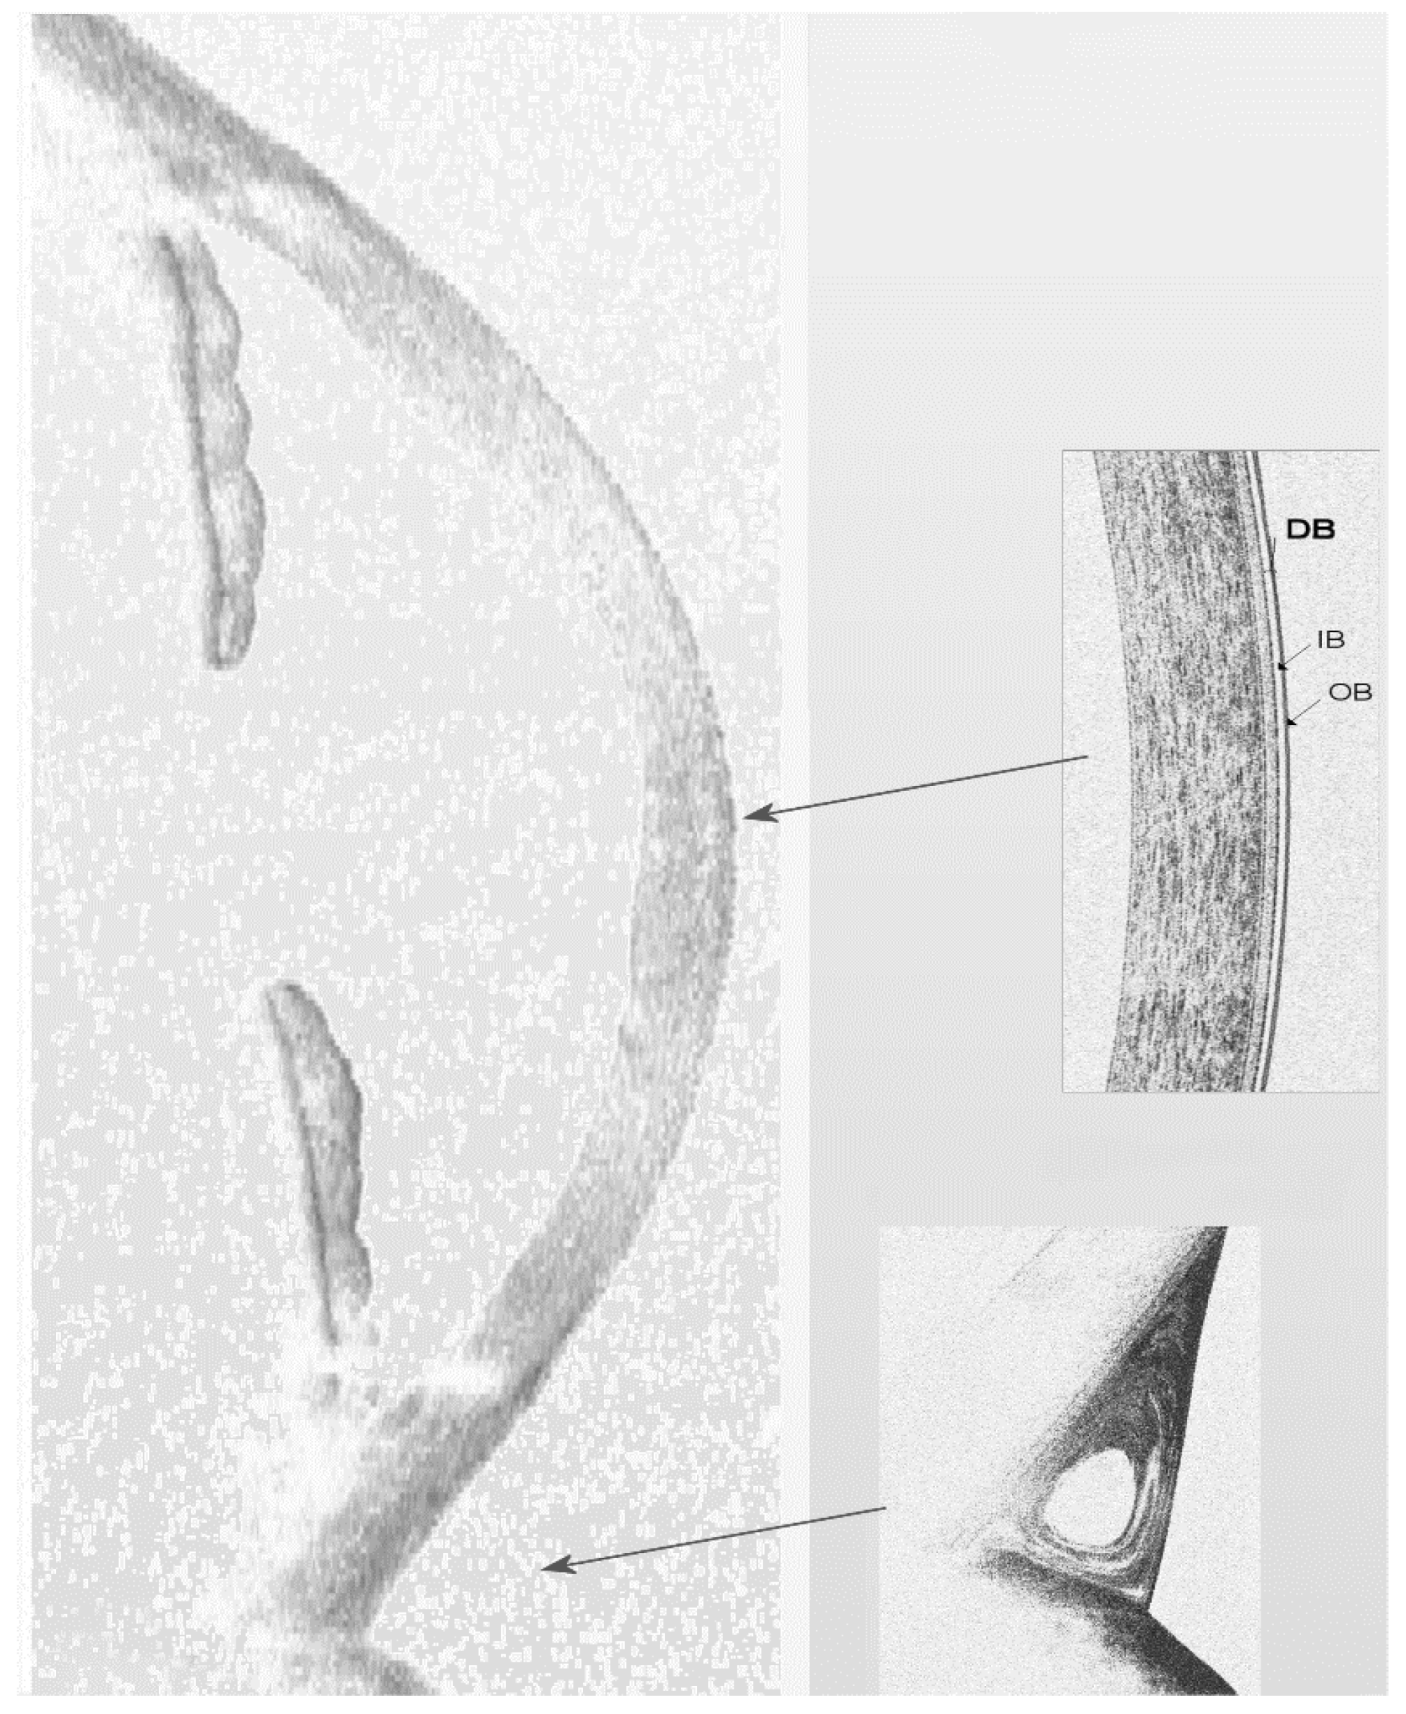

- Veres, A.; Tapasztó, B.; Kosina-Hagyó, K.; Somfai, G.M.; Németh, J. Imaging lid-parallel conjunctival folds with OCT and comparing its grading with the slit lamp classification in dry eye patients and normal subjects. Invest. Ophthalmol. Vis. Sci. 2011, 52, 2945–2951. [Google Scholar] [CrossRef] [PubMed][Green Version]

- Gumus, K.; Pflugfelder, S.C. Increasing prevalence and severity of conjunctivochalasis with aging detected by anterior segment optical coherence tomography. Am. J. Ophthalmol. 2013, 155, 238–242. [Google Scholar] [CrossRef] [PubMed]

- Qiu, W.; Zhang, M.; Xu, T.; Liu, Z.; Lv, H.; Wang, W.; Li, X. Evaluation of the effects of conjunctivochalasis excision on tear stability and contrast sensitivity. Sci. Rep. 2016, 6, 37570. [Google Scholar] [CrossRef] [PubMed]

- Allam, R.S.; Ahmed, R.A. Evaluation of the lower punctum parameters and morphology using spectral domain anterior segment optical coherence tomography. J. Ophthalmol. 2015, 2015, 591845. [Google Scholar] [CrossRef]

- Bizheva, K.; Hutchings, N.; Sorbara, L.; Moayed, A.A.; Simpson, T. In vivo volumetric imaging of the human corneo-scleral limbus with spectral domain OCT. Biomed. Optic. Express 2011, 2, 1702–1794. [Google Scholar] [CrossRef] [PubMed]

- Ghouali, W.; Hassani, R.T.; Djerada, Z.; Liang, H.; El Sanharawi, M.; Labbé, A.; Baudouin, C. In vivo imaging of palisades of Vogt in dry eye versus normal subjects using en-face spectral-domain optical coherence tomography. PLoS ONE 2017, 12, e0187864. [Google Scholar] [CrossRef] [PubMed]